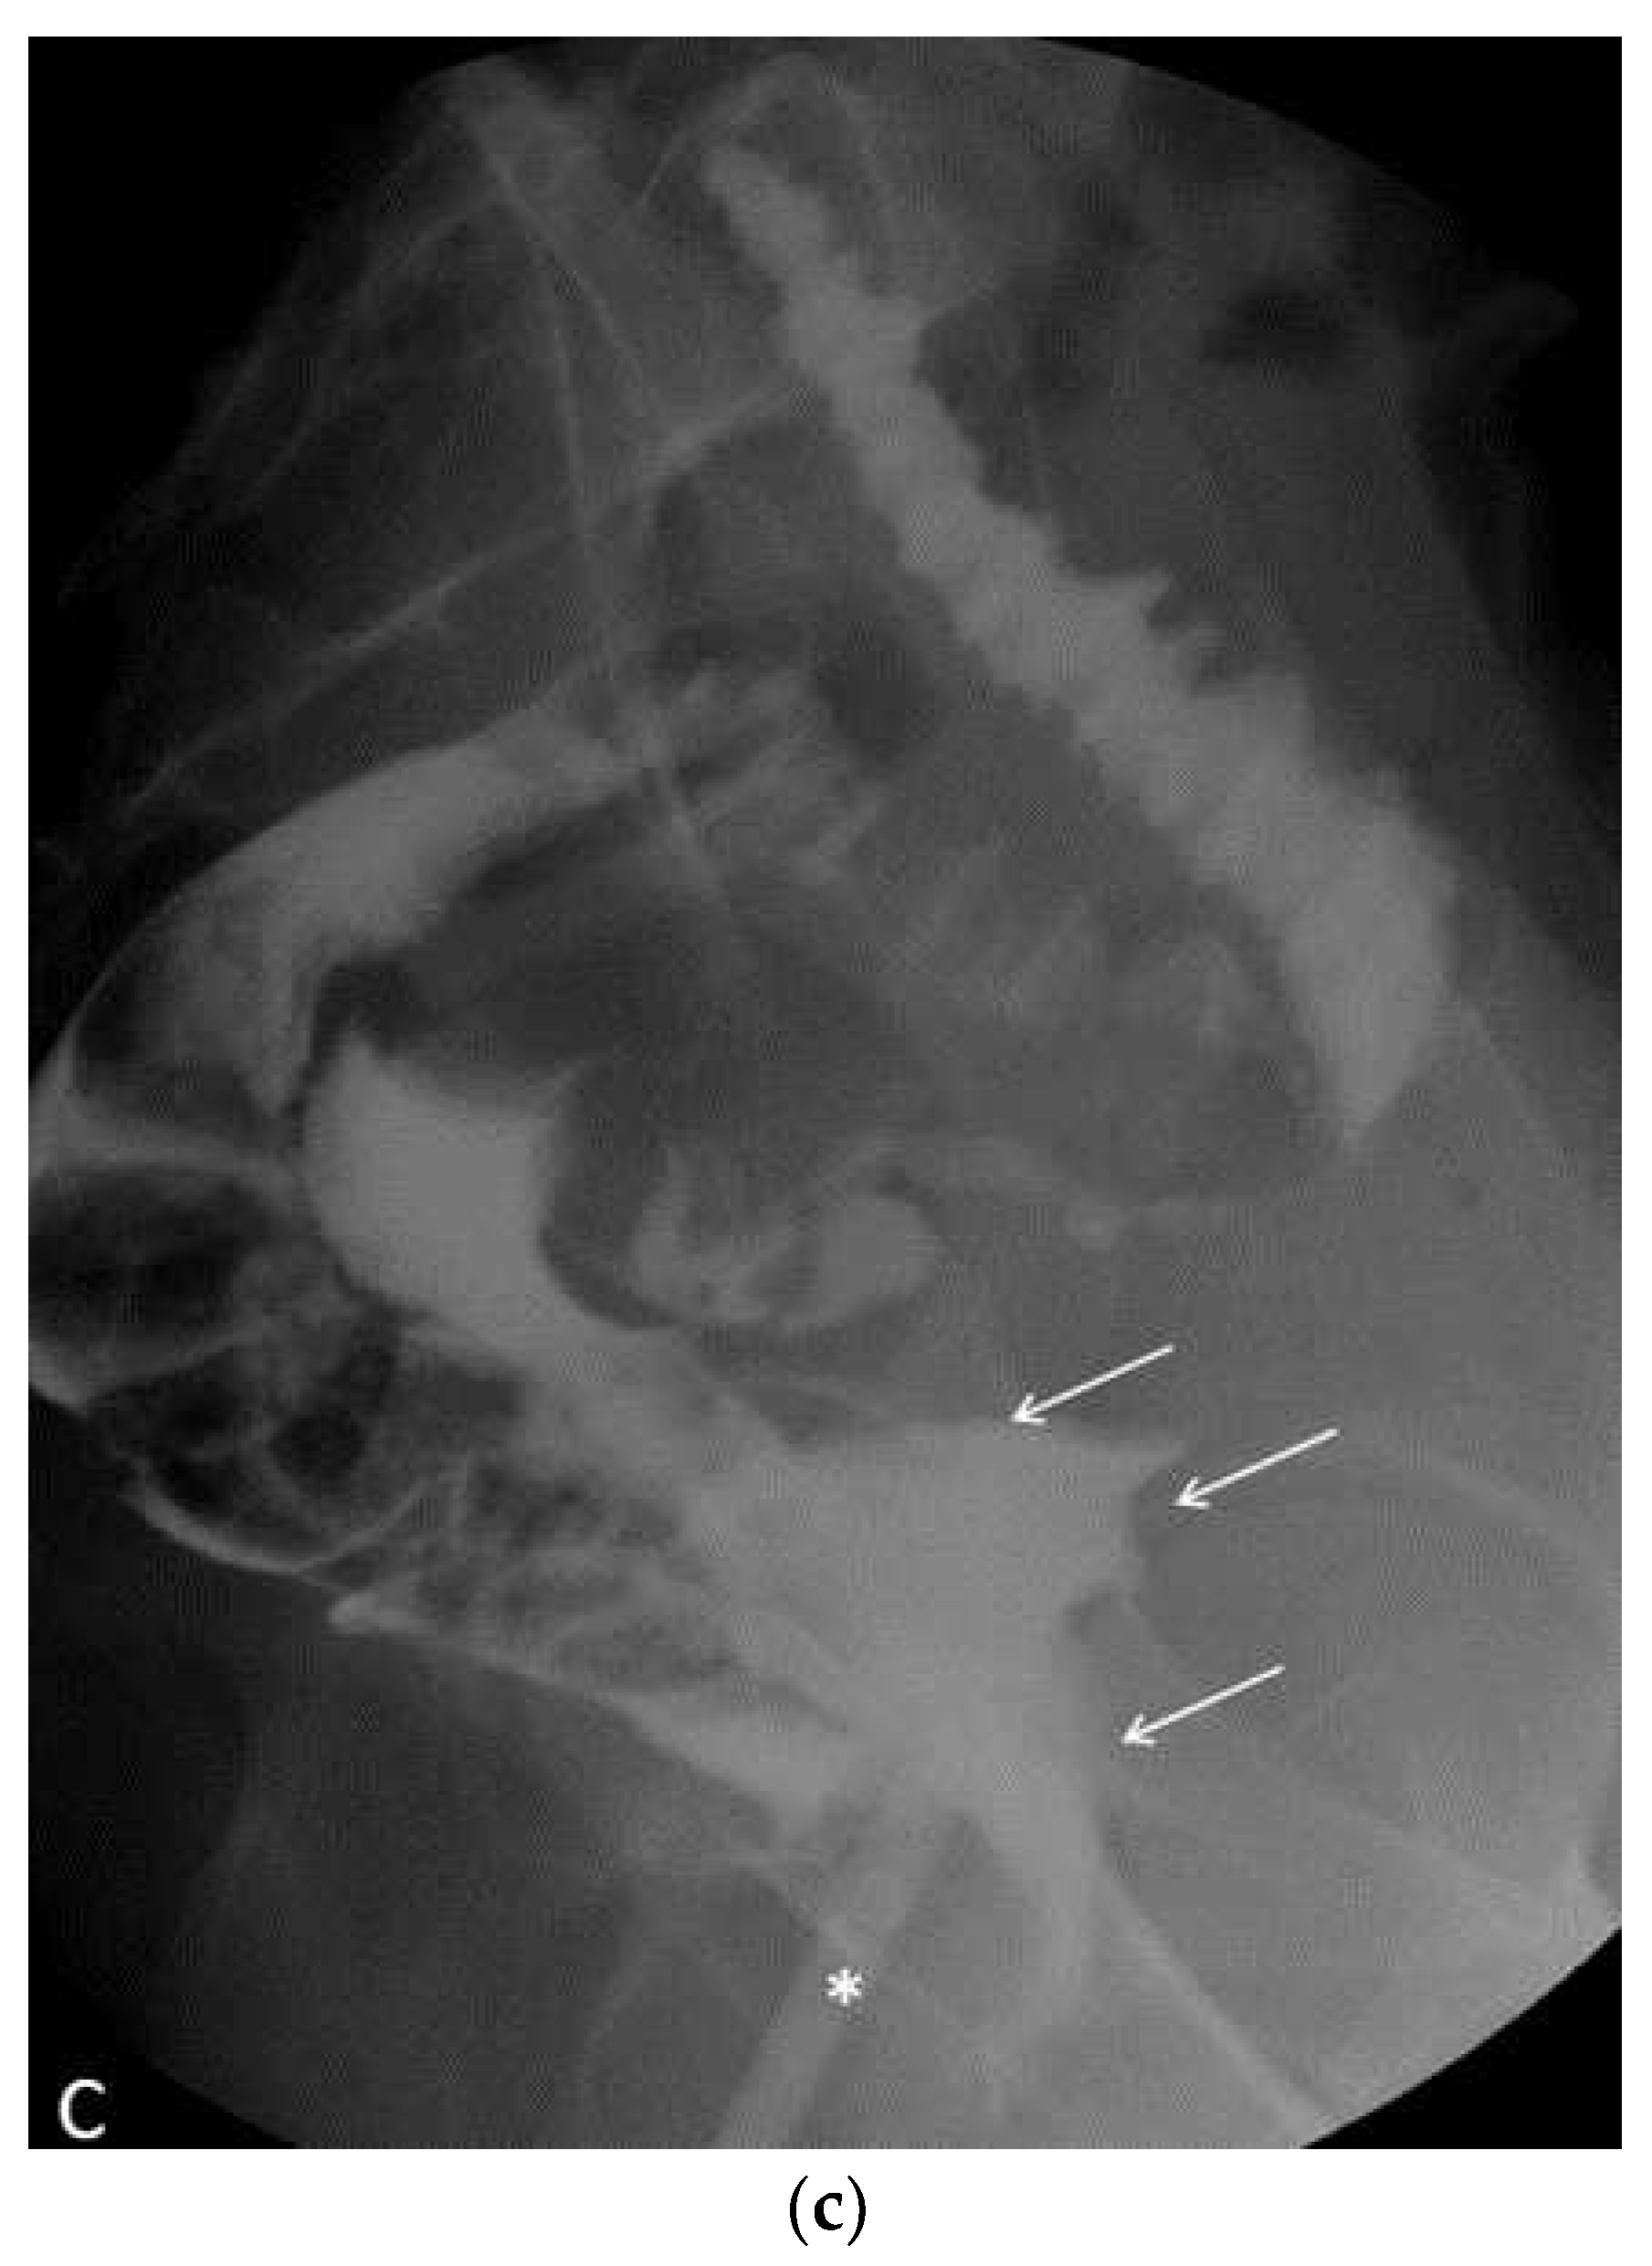

In the postoperative course, the patient experienced nonspecific symptoms: she remained afebrile, had mild pelvic pain at the site of the vaginal suture, which was managed with paracetamol as needed, and had diarrhea throughout the hospital stay. Only on the fifth postoperative day, malodorous secretions were observed in the vagina, and the patient was promptly examined for suspected vagino-rectal fistula. Immediate antibiotic therapy was initiated, and further diagnostic and radiologic tests confirmed the clinical suspicion of vagino-rectal fistula (Figure 6a–c), and the patient undergone adequate surgical treatment.

Figure 6. (a) Plain radiography shows free sub diaphragmatic air (white arrows). (b) Contrast enhanced CT. A small fistula (white arrow) connects the rectum with the upper portion of the vaginal canal. Diffuse thickening of soft tissues close to the mesorectal fascia is associated with a thin fluid layer (asterisks). (c) A frame of fluoroscopy obtained by single contrast enema performed with gastrografin. The contrast medium, injected transvaginally through a small tube (asterisk), spreads into the surrounding soft tissues (white arrows) and, to a lesser amount, into the rectum (arrowhead), confirming the presence of a pervious fistula.